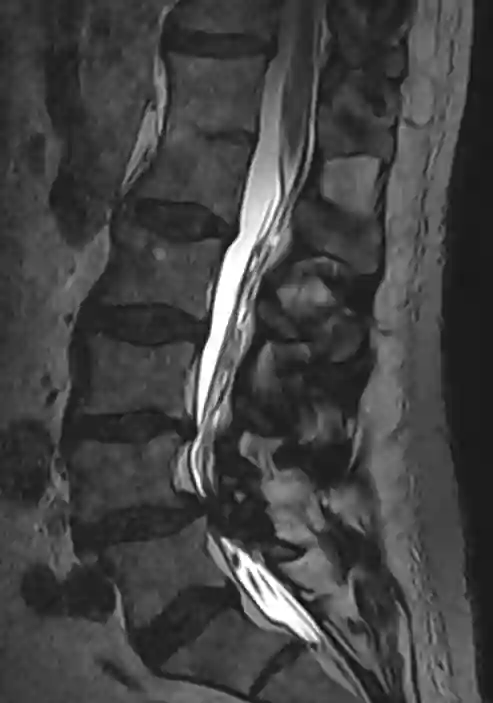

Blockwirbelbildung im MRT

Darstellung eines Blockwirbels zwischen LWK1 und BWK12 in einem sagittalen T2 MRT der Wirbelsäule.